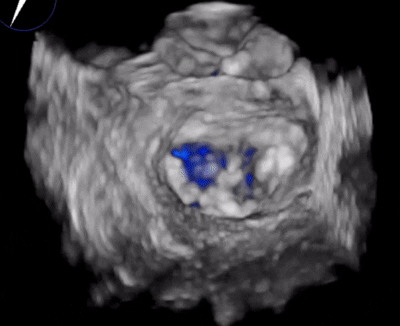

術(shù)前超聲

A3脫垂連枷(脫垂高度9mm,連枷高度:7mm),反流等級(jí)MR 4+(反流寬度11mm),有效瓣環(huán)面積MVA約6.3cm²。前瓣葉長(zhǎng)度23,后瓣葉長(zhǎng)度14.5mm,瓣環(huán)直徑AP 29mm。

4.3D圖像調(diào)整夾子位置及鐘向;